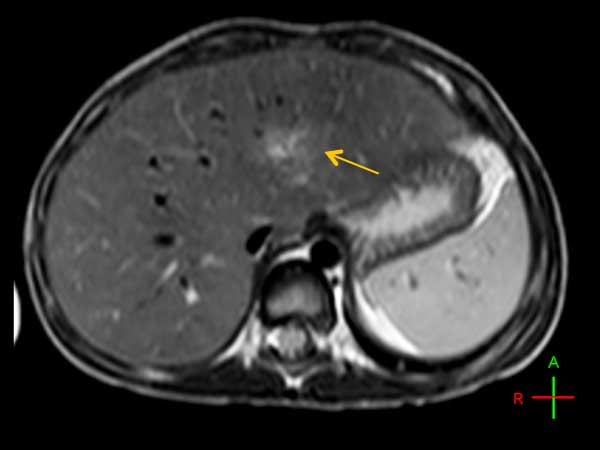

3 year old boy. Small liver lesion detected. Child was sedated but not under anesthetics.

Axial T2w TSE (with Resp. Navigator)